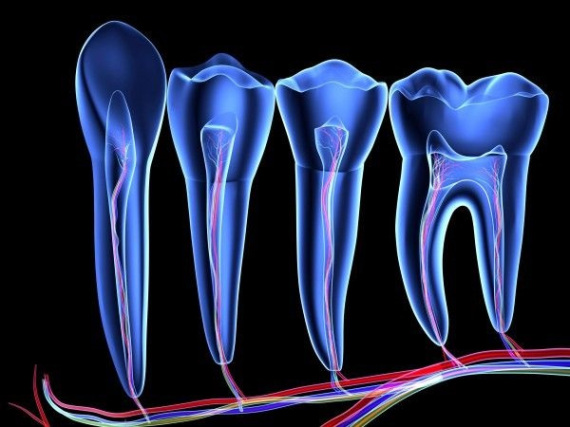

Эндодонтія

Очищення зубних каналів

Лікування запалення зубного нерву, дезінфекція та пломбування корневих каналів сучасними матеріалами.